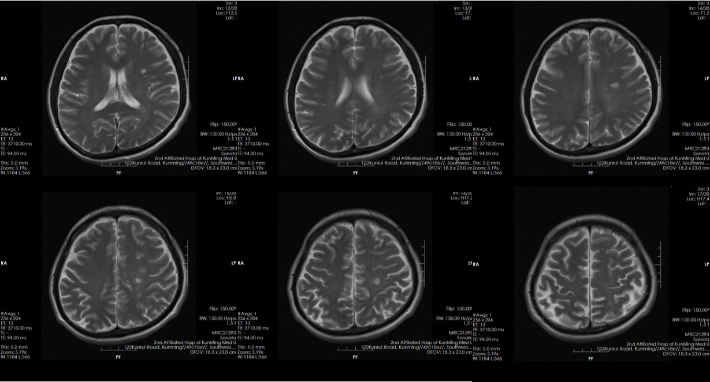

8月前起病时头颅磁共振

✔本例患者为症状性颅内动脉狭窄,已发生脑梗死(交界区点片状梗死,考虑为低灌注所致)

--无手术禁忌

--CTP有低灌表现

--DSA显示左侧颈内虹吸段狭窄约72%。前交通开放,右侧大脑前动脉通过前交通动脉向左侧大脑前动脉、大脑中动脉供血区有代偿供血。

--双抗治疗下仍有缺血症状发作。评估有手术指征,无手术禁忌。